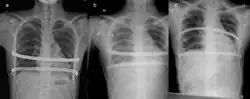

Iatrogenic hemothorax resulting from the Nuss procedure. A showing no hemothorax, b showing hemothorax, and c showing resolution after treatment.

Air in the chest (pneumothorax) is one of the more frequent complications. A chest tube may be required or aggressive breathing exercises and close monitoring may be adequate.

Other complications which may occur include hemothorax, pleural effusion, pericarditis, wound infection and pneumonia and acquired scoliosis.[6]: 340  Vigorous incentive spirometry is used to prevent pneumonia.[6]: 341  Some patients are allergic to one of the components of stainless steel.[6]: 341  As a result, allergy testing is now routinely done prior to surgery. In the event of an allergy, a titanium bar will be used.